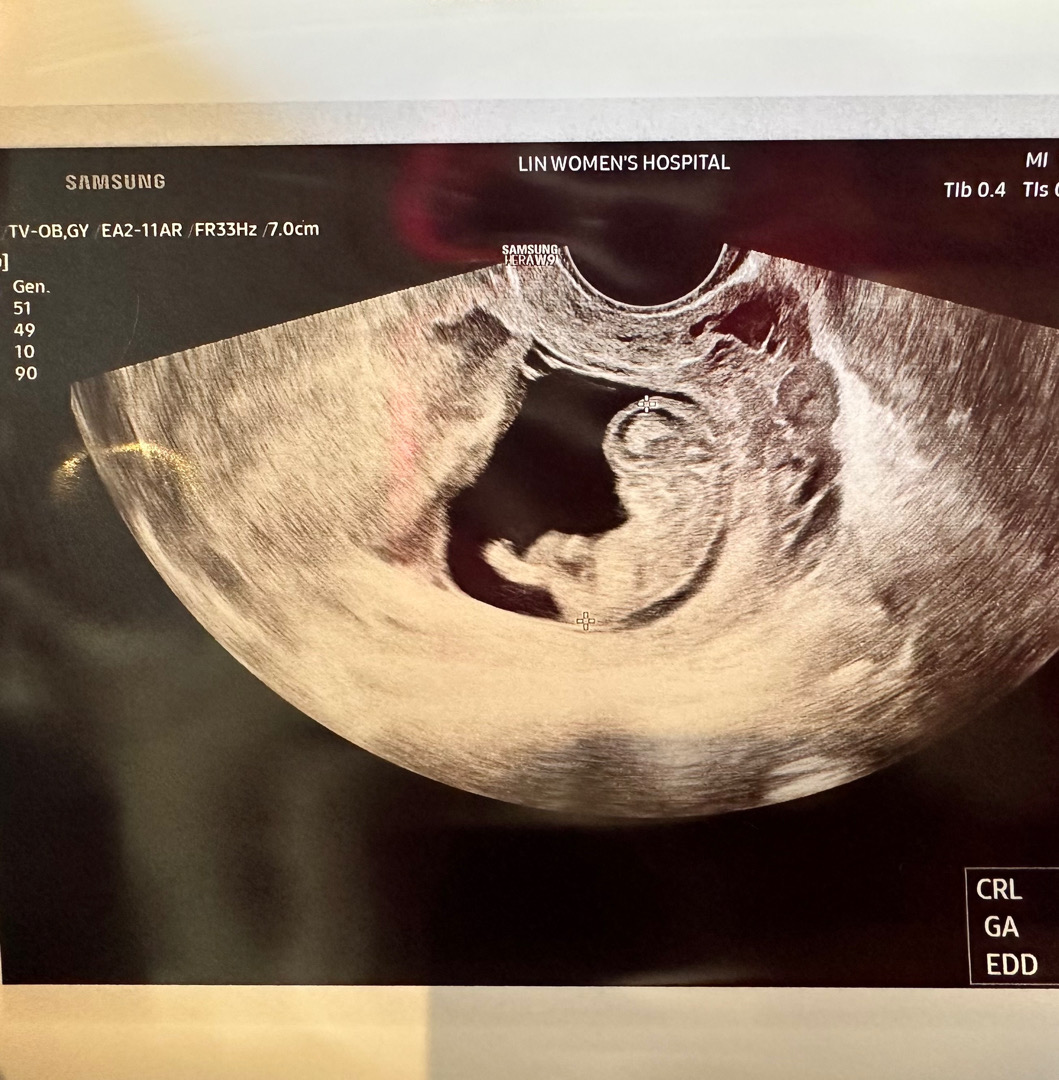

안녕하세요 이번에 둘째 임신했어요~ 첫째때는 이 시기에 입덧이 심해서 먹을 생각이 하나도 안 들었는데 둘째때는 입덧이 없어서 잘 먹는 편이에요 근데 또 많이 먹으면 오히려 속이 부대끼고 조금만 먹어도 배가 불러서 많이 못 먹긴 하거든요 그래서 저녁먹고 이시간되면 배가 고파요 배 고파서 속도 쓰린 것 같구요 아이를 위해서 먹는게 나을까요? 아님 그냥 자는게 나을까요? 둘째 엄마여도 이런 임신증상은 첨이라 모르겠네요 ㅎㅎ 촘파 사진은 10주 1일때 찍은거에요 선생님이 꼭 쇼파에 기대고 앉아있는 모습같다고 신기해 하셨네여 ㅎㅎ